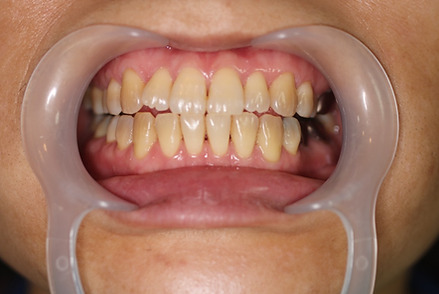

2ホワイトニング【治療例2】

治療前

治療後